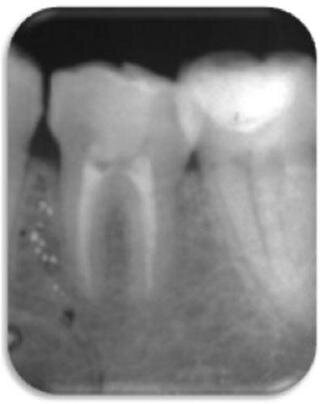

Autogenny przeszczep 3. trzonowców może stanowić doskonałą alternatywę dla odbudowy obszarów bezzębnych (Ryc. 1)1,2. Powszechnie twierdzi się, że leczenie kanałowe (RCT) autogennego przeszczepu zęba 36 powinno zostać przeprowadzone w czasie 14 dni przed rozpoczęciem poważnych reakcji zapalnych.7,8 W niniejszym opisie przypadku pacjent zgłosił się ponownie 6 miesięcy po zabiegu chirurgicznym z objawami zapalenia tkanek okołowierzchołkowych (AP) związanymi z przeszczepionym zębem (Ryc.2).

Pacjent zgłosił się ponownie dopiero po 6 miesiącach z objawami dyskomfortu podczas żucia, tkliwości opukowej, przejściowej opuchlizny oraz negatywnej reakcji na testy termiczne. Przeprowadzone badania radiograficzne potwierdziły wstępną diagnozę AP (Ryc. 2).

Jak potwierdza niniejszy opis przypadku, 6 miesięcy po przeszczepie widoczna była poważna reakcja zapalna – czas ten przekraczał wszystkie zalecenia dotyczące okresu na przeprowadzenie RCT.4 Może to również podkreślać znaczenie przestrzegania przez pacjenta ustalonego wcześniej protokołu.6